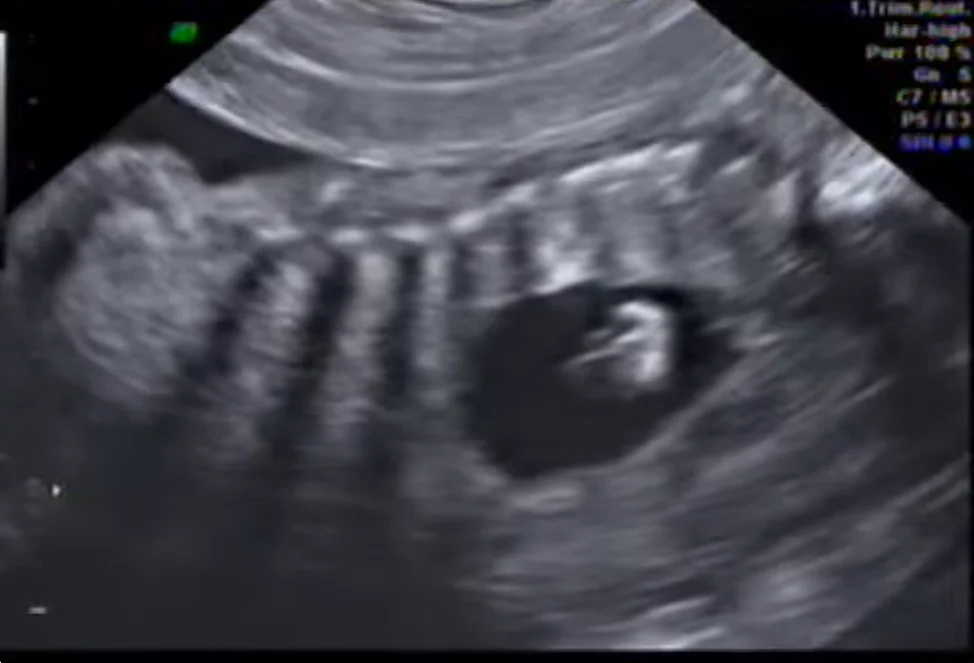

• IX. Ngực thai nhi

• Giải phẫu siêu âm ngực thai quý I

• Tràn dịch màng phổi thai quý I (Hydrothorax / Pleural effusion)

• Thoát vị hoành bẩm sinh quý I (Congenital diaphragmatic hernia- CDH)